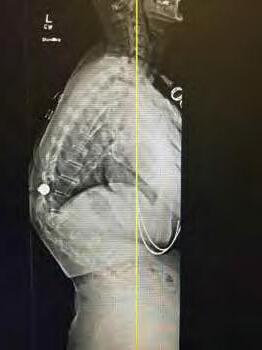

TOP 1% OR HIGHER ON NATIONAL EXAMS INCLUDING MOST RECENT BOARD RE-CERTIFICATION 30+ YEARS OF SPINE SURGERY EXPERIENCE DOUBLE BOARD-CERTIFIED 20+ YEARS AMERICAN BOARD ORTHOPEDIC SURGERY AMERICAN BOARD SPINE SURGERY PATRICK MCNULTY, MD F.A.B.O.S. • F.A.B.S.S. JOHNS HOPKINS FELLOWSHIP IN SPINE SURGERY 2 OFFICE LOCATIONS: 3012 South Durango Drive • Las Vegas, NV 89117 3175 Saint Rose Parkway, Ste 320 • Henderson, NV 89052 702-463-1424 • www.mcnultyspine.com • mcnultyteam@mcnultyspine.com LOWER BACK PAIN • NECK PAIN • SCIATICA • SCOLIOSIS• SPINAL STENOSIS SPINAL INJECTIONS • MINIMALLY INVASIVE SURGERY • KYPHOSIS • SPINAL RECONSTRUCTION MEDICOLEGAL EVALUATION/TREATMENT/EXAMINATIONS 27